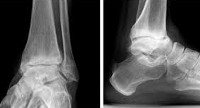

Диагноз выставляется на основании опроса, данных осмотра и результатов дополнительных исследований. Решающую роль в постановке диагноза и определении степени артроза играет рентгенография голеностопного сустава. Об артрозе свидетельствует сужение суставной щели, разрастание краев суставных поверхностей (остеофиты). На поздних стадиях выявляются кистовидные образования и остеосклероз субхондральной (расположенной под хрящом) зоны кости. В сложных случаях для более точной оценки состояния костных структур пациента дополнительно направляют на КТ голеностопного сустава, для исследования мягких тканей - на МРТ голеностопного сустава. При необходимости для выявления причины артроза и дифференциальной диагностики с другими заболеваниями назначают консультации смежных специалистов: невролога, ревматолога, эндокринолога.